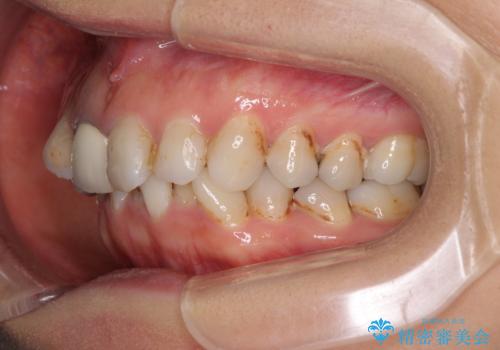

- 前歯の歯並びやむし歯治療の跡、奥歯の銀歯を気にして来院された患者様です。

インビザラインによる矯正治療の後に虫歯や銀歯をセラミックにて補綴することとしました。

前歯のむし歯治療の跡や奥歯の目立つ銀歯がなくなり、明るい口元になりました。